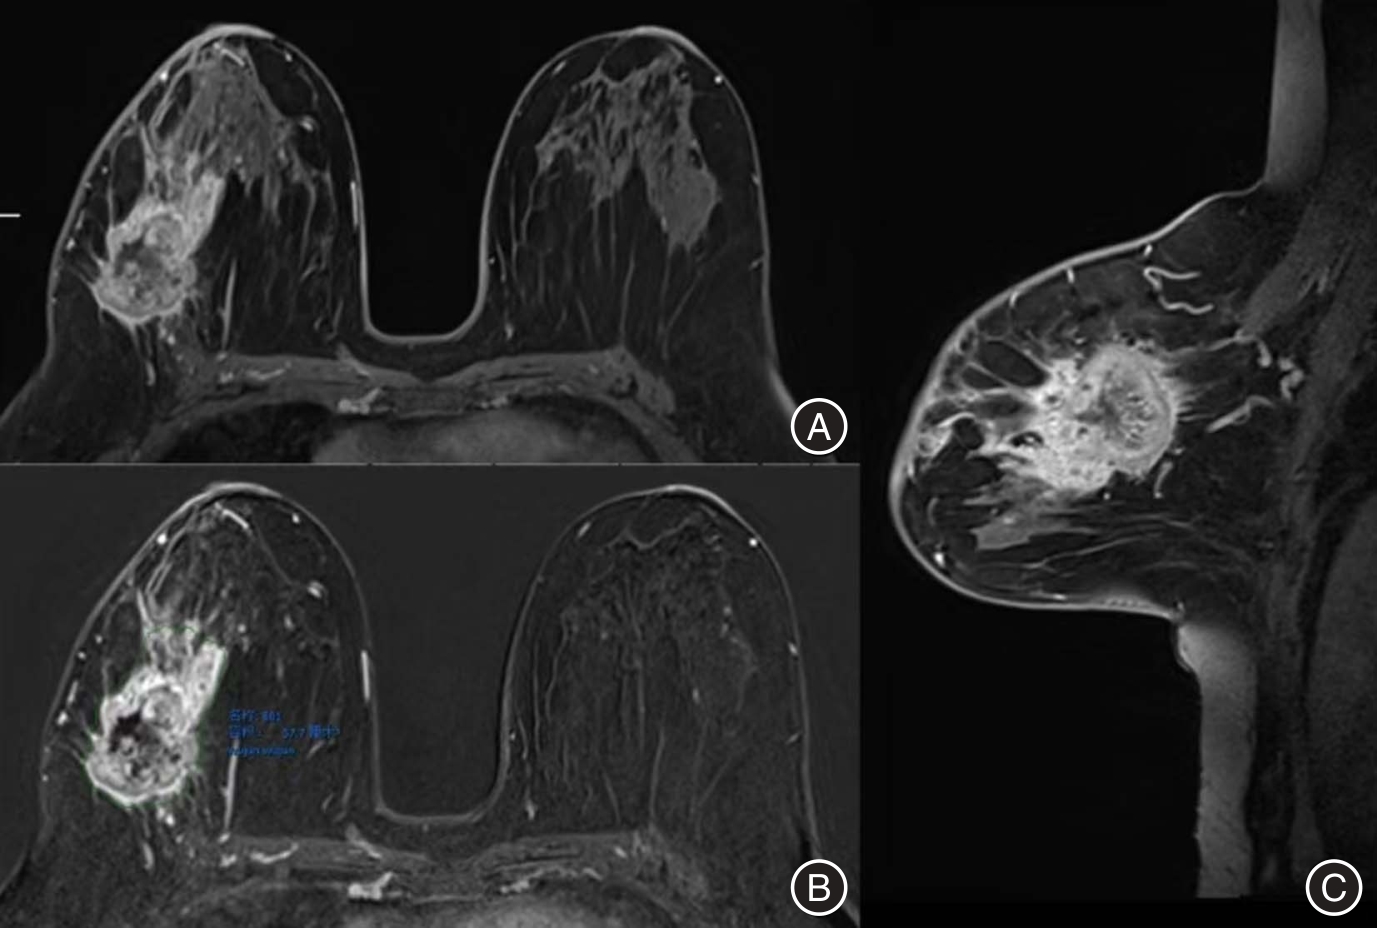

目的 比较乳腺磁共振(MRI)三种测量方法——RECIST 1.1标准、最优法和三维(3D)体积测量法在乳腺癌新辅助化疗(NAC)疗效评估中的诊断性能差异,筛选更具临床实用性的影像学评估方式。 方法 纳入2019—2023年间接受NAC及手术治疗的乳腺癌患者110例。化疗前后分别于1周内完成乳腺MRI,采用RECIST 1.1、最优法和3D体积测量法进行疗效评估,以MP病理分级为金标准。比较3种方法的敏感度、特异度、准确性及受试者工作特征曲线(ROC)下面积(AUC),并通过Delong检验进行统计比较。 结果 RECIST 1.1、最优法和3D测量法的AUC分别为0.768、0.795和0.883,3D体积测量法显著优于其他两种方法(P < 0.05)。3D法在敏感度(98.9%)、特异度(77.8%)和准确性(95.5%)方面均表现最优。最优法在部分指标上亦优于RECIST 1.1。 结论 3D体积测量法在乳腺癌NAC疗效评估中显示出最佳的诊断性能,具有更高的临床应用价值。最优法相较于传统RECIST 1.1方法也表现出更优的判别能力,是资源受限情况下的可行替代方案。

Objective To compare the diagnostic performance of three breast MRI measurement methods—RECIST 1.1, the optimal method, and three-dimensional (3D) volumetric assessment—in assessing the efficacy of neoadjuvant chemotherapy (NAC) in breast cancer patients, with the objective of identifying the most clinically practical approach. Methods A total of 110 breast cancer patients who underwent NAC followed by surgical treatment between 2019 and 2023 were included in the study. Breast magnetic resonance imaging (MRI) was conducted within one week before and after the completion of NAC. Tumor response was evaluated using RECIST 1.1 criteria, widely recognized as the optimal method, as well as 3D volume measurement. Pathological response was determined according to the Miller-Payne grading system. Sensitivity, specificity, accuracy, and the area under the receiver operating characteristic curve (AUC) were computed and compared using the DeLong test. Results The AUC values for RECIST 1.1, the optimal method, and 3D volumetric assessment were 0.768, 0.795, and 0.883, respectively. The 3D volumetric assessment exhibited significantly better discriminative performance (P < 0.05), with the highest sensitivity (98.9%), specificity (77.8%), and accuracy (95.5%). Additionally, the optimal method demonstrated superior performance over RECIST 1.1 across multiple parameters. Conclusions 3D volumetric measurement demonstrates superior performance compared to RECIST 1.1 and the optimal method in evaluating the response to NAC, offering a more accurate and comprehensive assessment tool. Additionally, the optimal method shows advantages over RECIST 1.1 and may serve as a practical alternative in settings where 3D software is not available.